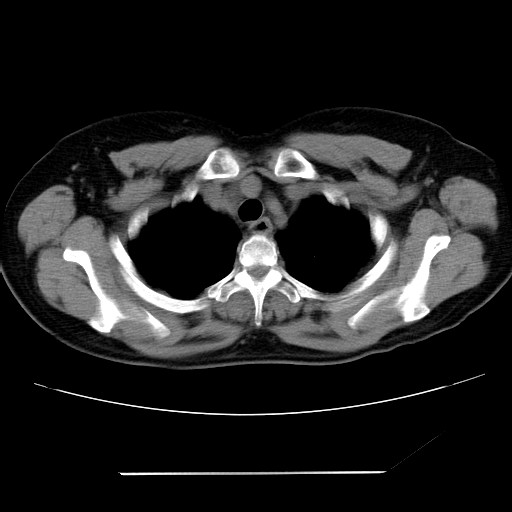

标题: CT24018:女性,62岁,咳嗽4年,无热,胸部CT扫 [打印本页]

女性,62岁,长期咳嗽,既往从事工作有粉尘接触,有高血压病史,110/150mmhg,近日咳嗽加重,脸面浮肿,请大家帮看下,

1、尘肺;2、慢性支气管炎合并肺部感染;3、心影增大(左房、左室大),考虑高血压性心脏病。

心包有积液吗?

慢支并肺部炎症;右肺结核球?主肺动脉、右肺动脉影不宽,右心室不大,不支持肺心病;无心包积液。